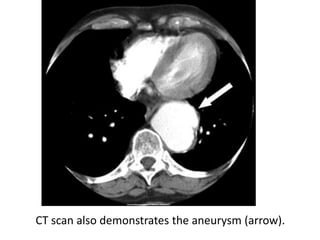

CT scan also demonstrates the aneurysm (arrow).

CT scan alsodemonstrates the aneurysm (arrow).